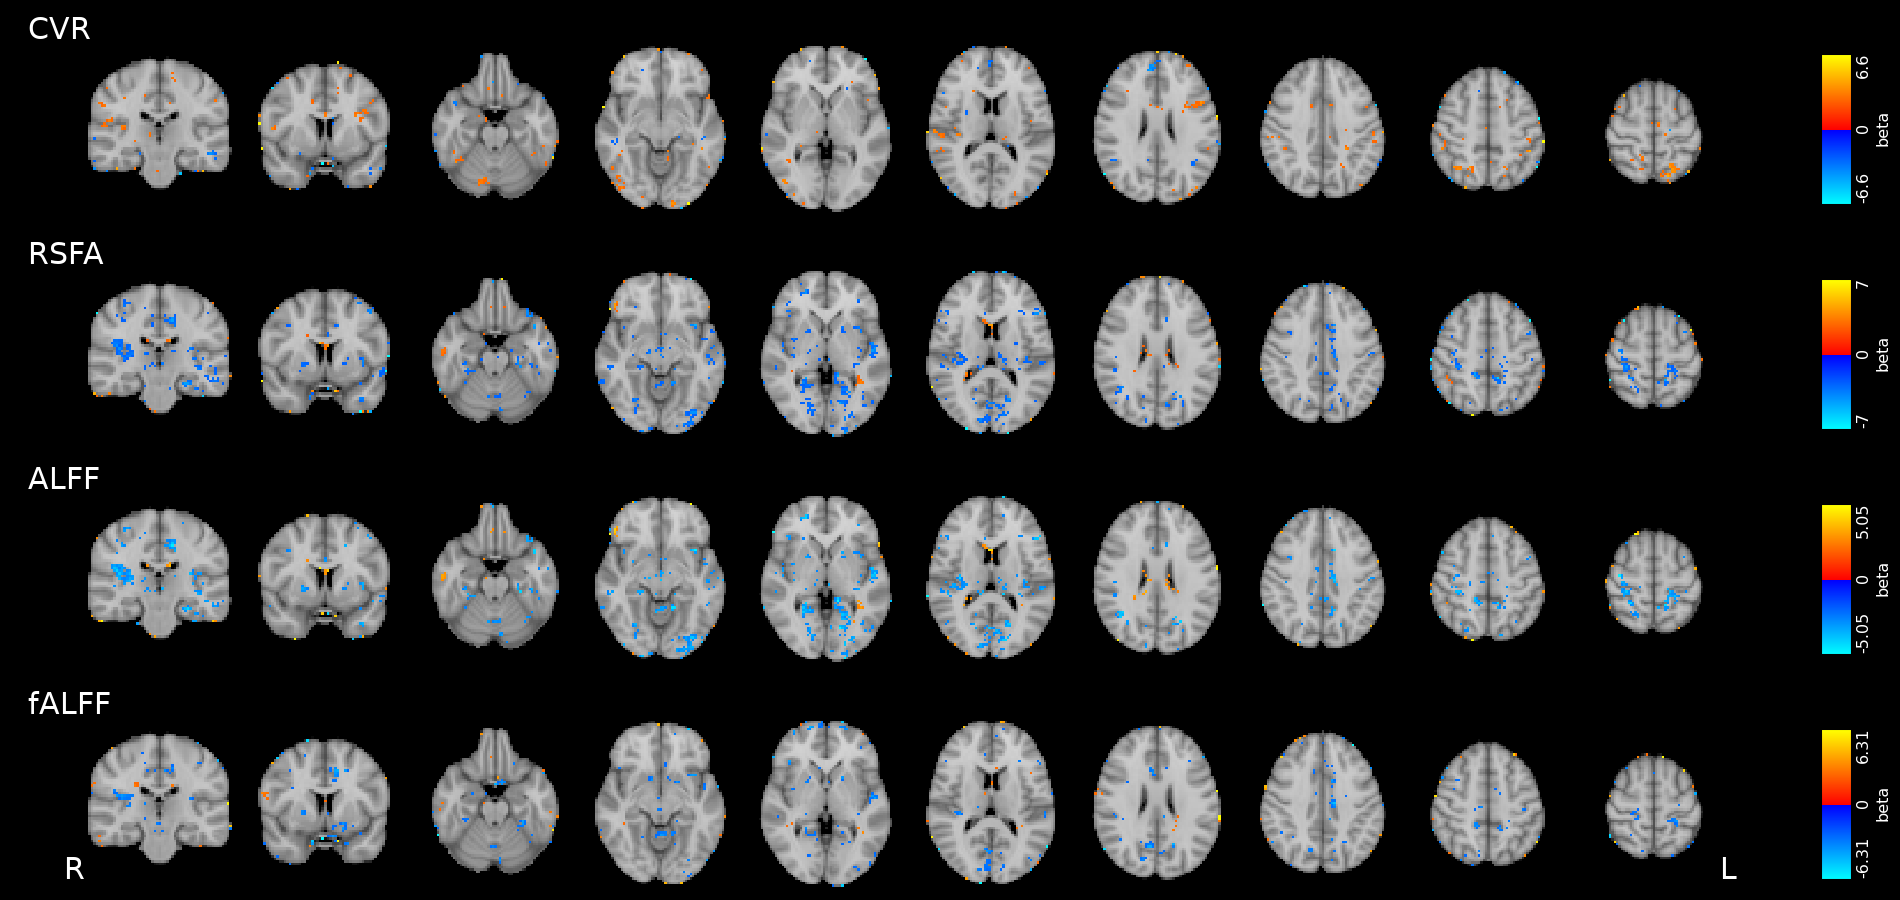

Data

- The first RS of the session

- A motor task

- A Simon task (executive functions)

We preprocessed RS, motor, and Simon data similarly to CVR

We computed:

- RSFA, ALFF, and fALFF from the first RS session

- task Induced Activation (tIA) of Motor task, as each movement vs sham

- tIA of Simon task, considering congruent or incongruent responses

- RSFA, ALFF, and fALFF from the first RS session

- task Induced Activation (tIA) of Motor task, as each movement vs sham

- tIA of Simon task, considering congruent or incongruent responses

We selected:

Methods: effect of CVR on fMRI

Results were thresholded at \(p<0.05\) after controlling for false discovery rate³

(then at \(p<0.001\) uncorrected)

1. Chen et al. 2013 (Neuroimage); 2. Golestani et al. 2016 (NeuroImage); 3. Benjamini et al. 2006 (Biometrika)

We used 3dLMEr¹ to set up the following LME models voxelwise (R syntax):

- \(RSF \sim cvr + (cvr|session) + (cvr|subject)\)

- \(tIA \sim RSF + (RSF|session) + (RSF|subject)\)

- \(tIA \sim cvr + (cvr|session) + (cvr|subject)\)

We used the first model considering the average GM value of RSF and CVR²

- \(RSF \sim cvr + (cvr|session) + (cvr|subject)\)

- \(tIA \sim RSF + (RSF|session) + (RSF|subject)\)

- \(tIA \sim cvr + (cvr|session) + (cvr|subject)\)

Results: CVR, RSF, and tasks

Motor task

Simon task, congruent responses

Simon task, incongruent responses

The relationship between CVR, RS fluctuations, and tIA

might be highly subject specific

or absent altogether.

- We did not observe a statistically significant effect of CVR on RS fluctuations, or of CVR and RS fluctuations on task induced activity, most probably due to the high variability between subjects

-

The failure of generalisation of previous observations might be related to different methods, but whether this is related to a better denoising and signal quality or to a possibly non optimal setting (e.g. compared to gas challenges) is uncertain

-

A different statistical perspective (i.e. Bayesian) is required to exclude any relationship between CVR and RS fluctuations, and further analyses are required to improve the agreement between CVR and RS fluctuations